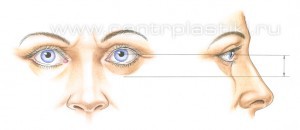

Это глубоко ошибочное мнение – современную пластическую операцию на веках, ни в коем случае, нельзя считать простой операцией. Хирургические методики блефаропластики (пластики век) в настоящее время развились (как самолетостроение) и стали значительно более сложными по сравнению с традиционным удалением “избытков кожи и жира”, которое выполнялось раньше всем пациентам подряд. В основном, это связано с тем, что в последние годы случилась, по-сути, революция во взглядах и подходах пластических хирургов к омоложению век – за последние два десятилетия было детально описано анатомическое строение этих областей лица и механизм их старения. Что привело пластических хирургов во всем мире к изменению техники выполнения омолаживающих операций на веках. Так, еще несколько десятилетий назад удаление кожи, мышцы, и жировой клетчатки, всем пациентам подряд, при стандартной блефаропластике (пластике век), которую выполняли многие пластические хирурги, зачастую приводило и приводит к неудовлетворительным результатам – вызывая западения век и придавая векам возрастной или «трупный» вид (Рис. 1-2)

Рис. 2. Запавшие нижние веки после стандартной блефаропластики («трупный» вид) – произведено удаление внутриорбитального жира Современные методики блефаропластики подразумевают не удаление а, в большинстве случаев, сохранение или перераспределение внутриорбитального жира, подъем вверх опустившихся под действием силы тяжести тканей век, добавление взятой у того же пациента жировой ткани или введение в область век наполнителей, на основе гиалуроновой кислоты и лишь иногда – удаление жира. Что и позволяет в большинстве случаев вернуть векам молодость, объем и хороший внешний вид. Рис. 3